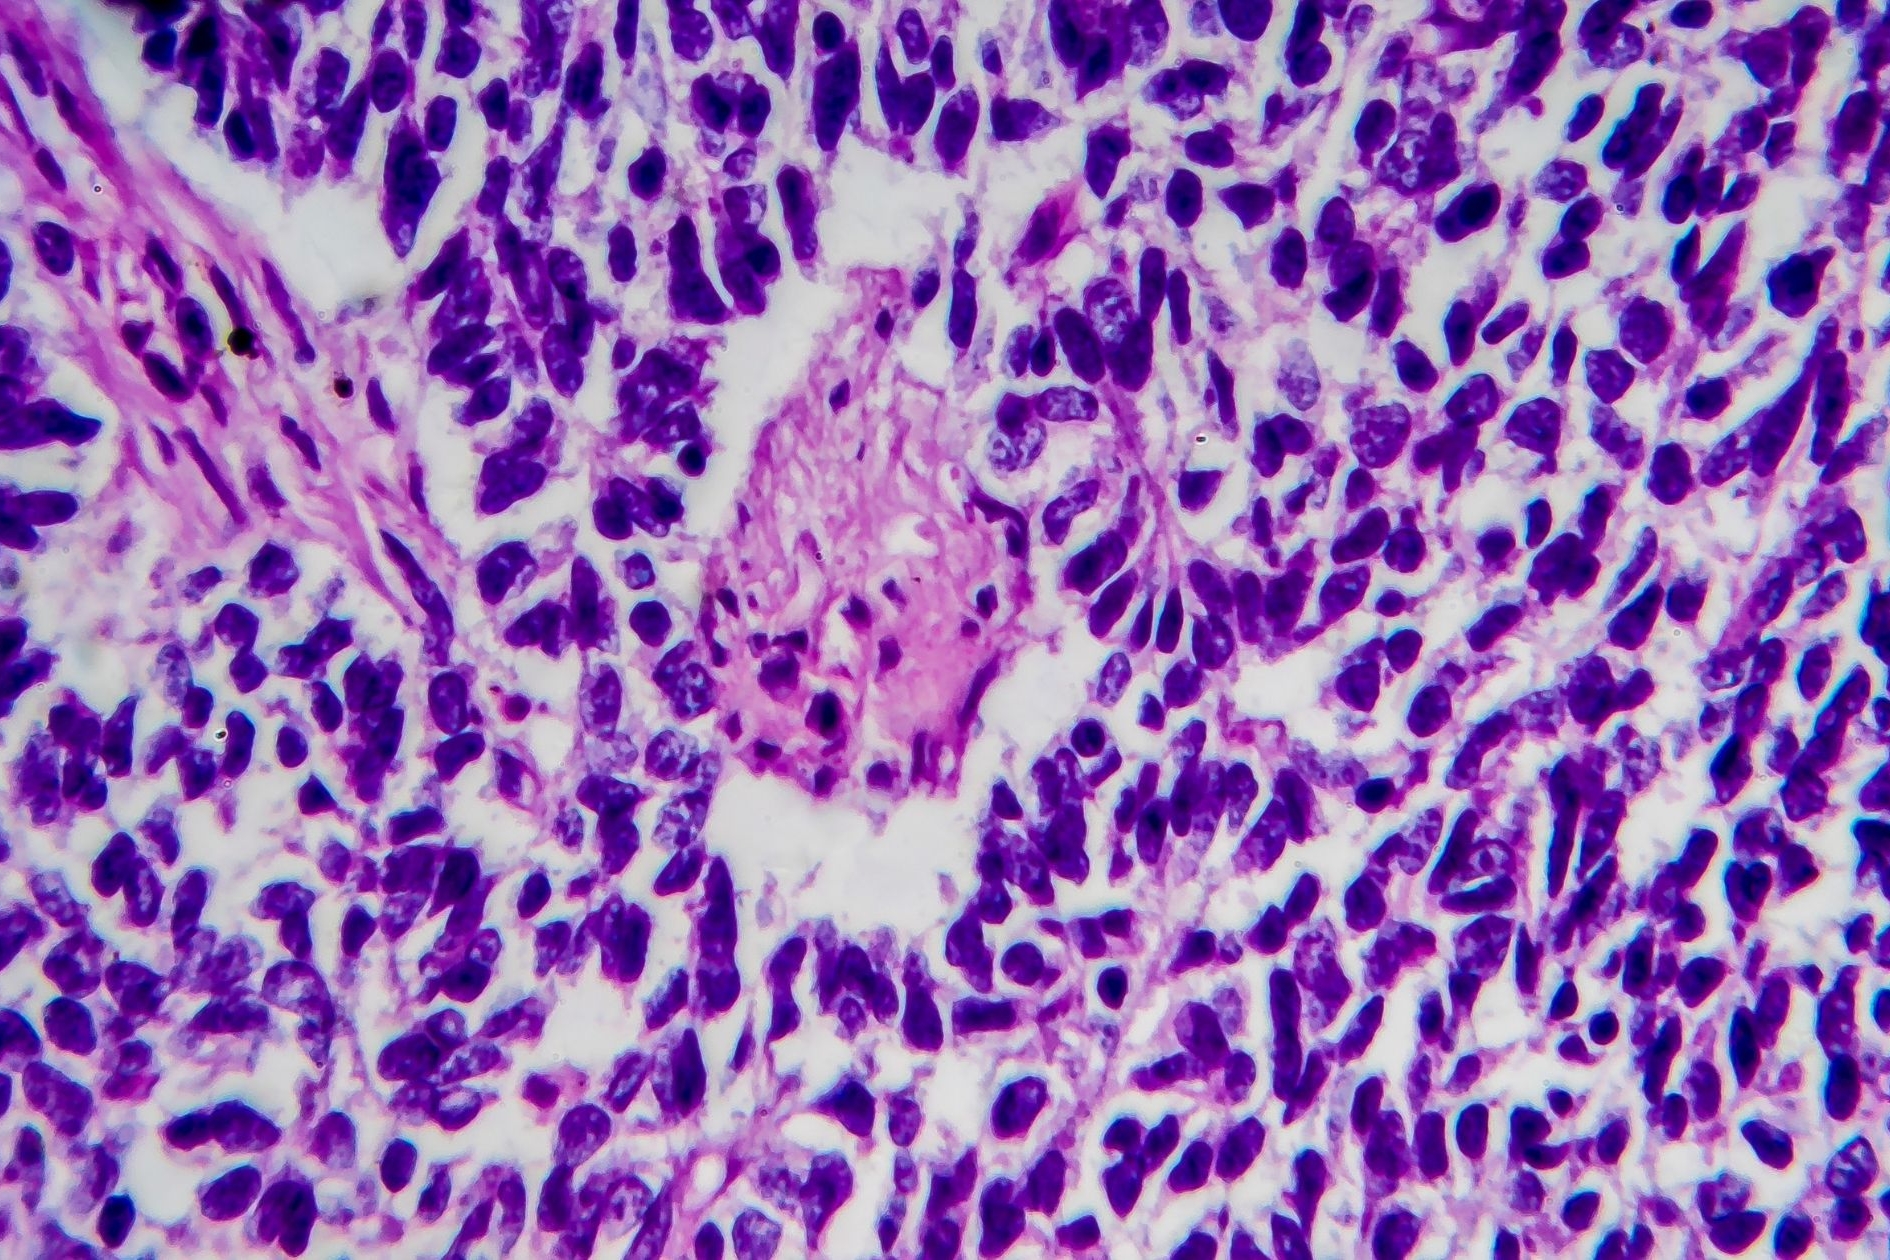

Tumor Markers in the General Practice